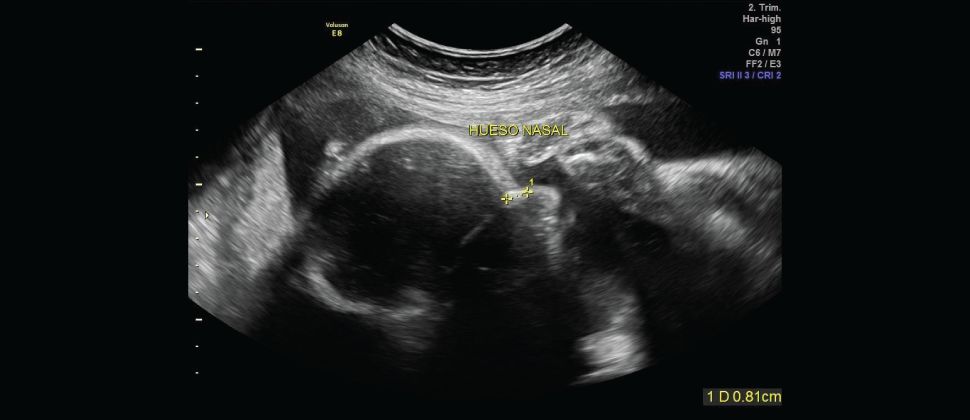

Consiste en que se realice un estudio ecosonográfico para detectar alteraciones que pudiesen sugerir la presencia de Anomalías Cromosómicas.

Los bebés con problemas cromosómicos manifiestan ciertos cambios anatómicos y funcionales muy puntuales que pueden ser detectados durante este período.

Se detectan algunos marcadores específicos que tienen la mayor capacidad de detección. Los marcadores específicos son:

Pliegue Nucal, Hueso Nasal y Ductus Venoso, entre otro.